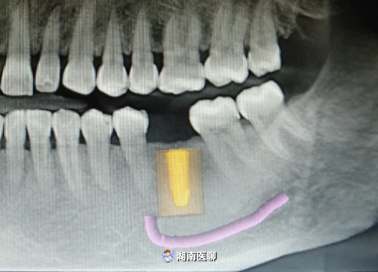

(種植術(shù)后cbct)

(術(shù)前種植設(shè)計(jì))

術(shù)后,經(jīng)口腔CBCT檢查,植入的種植體的三維方向都十分契合。